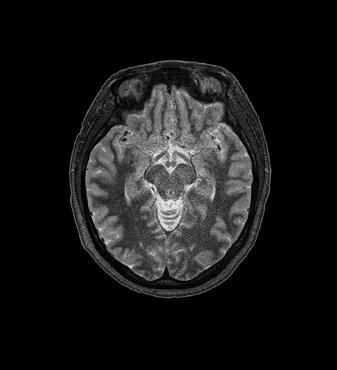

3D FLAIR with DLR. 3D FLAIR Original image. 100s, 0.5x0.5x0.6mm reconstructed

In particular DLR has an important clinical impact in anatomical regions that require a very high resolution, for example parts of the hippocampus and the claustrum.

“The DLR brings a spatial resolution that I have never seen before in neurologic imaging. I recently pointed out a brain area, for example the claustrum, that is almost invisible on standard MRI images even with very high resolution or high field devices. However, thanks

to the DLR we could highlight this kind of brain anatomy. So, indeed, there is a considerable advantage to using this technique.” Prof. Dousset said.

Prof. Tourdias worked at 7T to visualise extremely fine structures of the hippocampus while at Stanford. With DLR, he can now do this task with a 3T. “When we compared the images we realized that by pushing the 3T machine and processing with DLR that we were able to achieve a similar result to what we could achieve with 7T. I think this is the main surprise of the technology.” he said.

Brain – Hippocampus

Brain Atlas SPEEDER Head/Neck, 3D FLAIR, AiCE, Res: 1 x 1 x 1.1 mm, Scan time: 4:55 min.